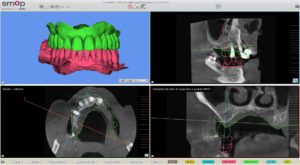

La planification implantaire a été réalisée sur le logiciel SMOP. Les empreintes ont été superposées avec le cone beam du patient.

Les implants ont été posés virtuellement, ce qui a permis au praticien d’évaluer la possibilité d’extraire, implanter et mettre en charge immédiatement lors d’une même séance.

Une fois la planification validée, un guide implantaire SMOP a été dessiné et imprimé (imprimante STRATASYS poly-jet avec précision à 16 microns ).

Le praticien a choisi de poser 2 implants Thommen en FULL GUIDED.